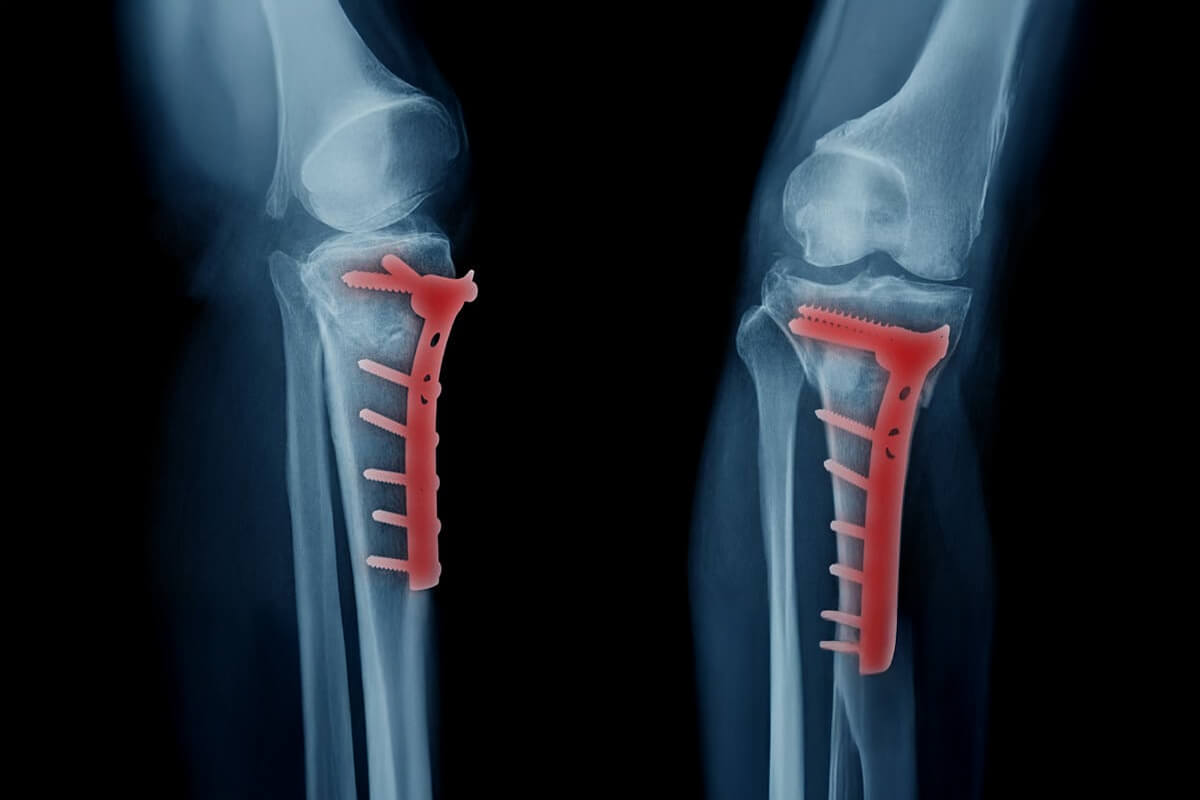

La osteosíntesis es el tratamiento quirúrgico de fracturas, logrando reducir y fijar la lesión en forma estable. Para ello se utilizan diferentes dispositivos tales como placas, clavos, tornillos, alambre, agujas y pines, entre otros.

Esto tiene relación con el uso de alta tecnología en los procedimientos, como la disponibilidad de equipos de radiología transoperatoria o el uso de implantes e instrumentales diseñados específicamente para cada porción del esqueleto y/o tipos diferentes de fracturas.